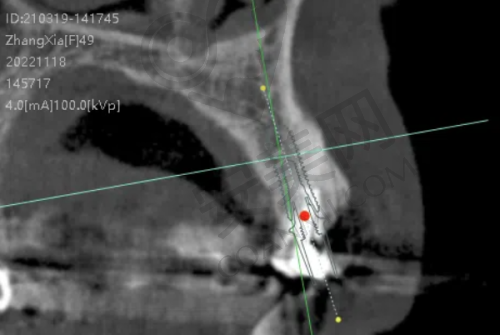

术前检查:患者到长春中诺口腔后,医生首先会对患者的口腔进行全方面的检查,包括口腔X光片、CT扫描等,以了解患者的牙槽骨情况、牙齿缺失情况以及口腔健康状况。根据检查结果,医生会评估患者是否适合进行种植牙手术,并制定个性化的种植方案。